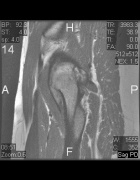

K.T. - 28 year old female with intermittent left hip pain for several years; she began having more frequent and intense pain a few months ago, prompting her to seek treatment

Zoom image: Radiological image Radiological image.